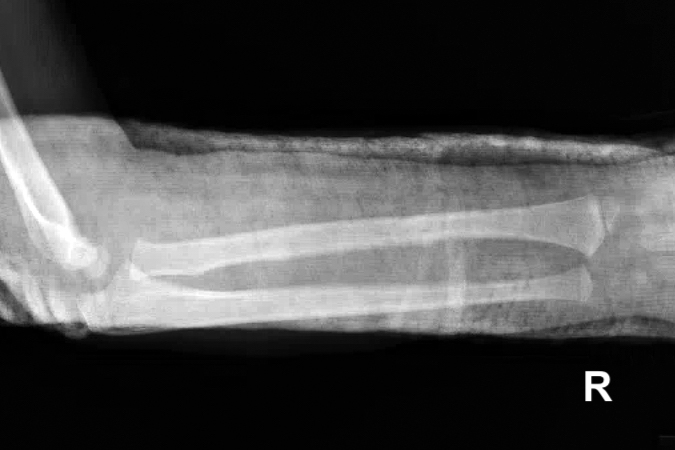

Galeazzi fracture

- Also known as a reverse Monteggia fracture or Piedmont fracture, the Galeazzi fracture is fracture of the middle to distal third of the radial shaft combined with a subluxation or dislocation of the distal radioulnar joint (DRUJ).12,13

- The Galeazzi fracture is considered a true forearm axis injury because of concomitant bone and soft tissue injuries. The triangular fibrocartilage complex (TFCC) and/or interosseous membrane (IOM are particularly at risk and their injury can contribute to forearm instability.12,14

- These injuries typically result from direct impact to the radius with forearm pronation. When a patient sustains a radial shaft fracture in the middle to distal third of the bone, the possibility of an associated DRUJ injury should be investigated.12,14

- Galeazzi fractures are more common in pediatric patients than adults. In children and adolescents, they are usually caused by sports injuries, falls from a height, or motor vehicle accidents.11,13

Imaging13

- Radiology studies - X-ray

- Anteroposterior (AP) and lateral views are usually sufficient, but an oblique view may help to better classify the injury and define a fracture line that is present but not apparent on the AP and lateral views.

- Because a coexistent joint injury is always possible, the distal wrist joint and elbow joint should always be included on the forearm X-rays or X-ray separately.